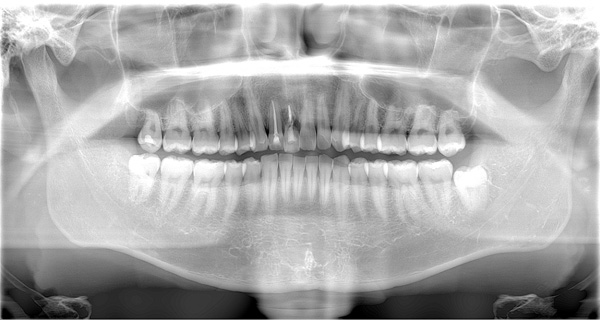

| 年代・性別 | 50代 男性 |

|---|---|

| 主訴 | 右上下の歯が痛い |

| 治療期間 | 約12ヶ月 |

| 費用 | 2,500,000円 |

| 治療内容 | インプラント、骨造成、結合組織移植、セラミック修復 |

| 治療に伴うリスク | インプラント周囲炎 セラミックの破折、脱離 |